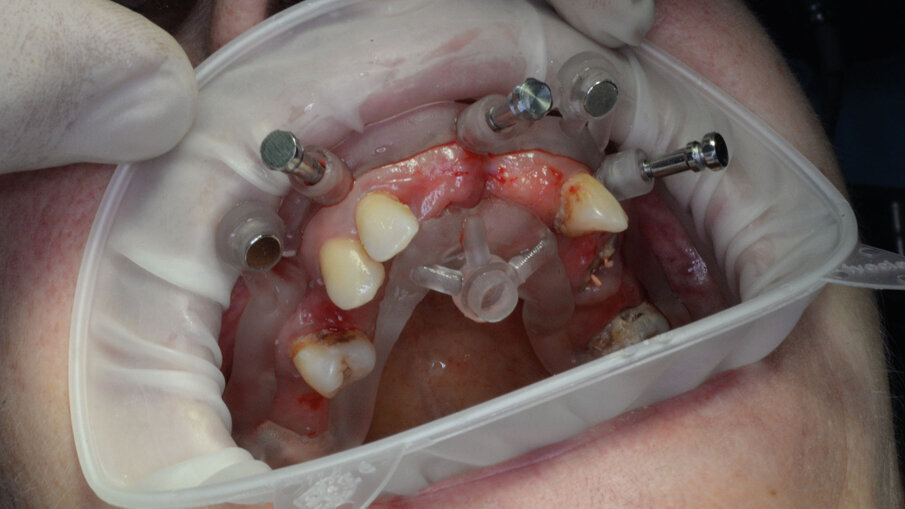

La paziente, una donna di 69 anni in buono stato di salute generale e senza terapie farmacologiche in corso, presentava una condizione orale fortemente compromessa caratterizzata da molte estrazioni dentali pregresse, una dentatura residua gravemente danneggiata da carie distruttive e numerosi processi infiammatori apicali e periapicali, che comportavano una severa mobilità della maggior parte dei denti presenti (Figg. 1, 2). La paziente utilizzava già una protesi parziale mobile superiore, la quale aveva causato nel corso degli anni un’ampia area di decubito palatale (Fig. 3). Data la compromissione estetica e funzionale dell’intero apparato masticatorio, si è deciso di procedere con una riabilitazione mediante una protesi avvitata supportata da impianti.

Per la realizzazione delle dime chirurgiche abbiamo utilizzato il nuovo modulo Sculpt rilasciato per lo stesso software di chirurgia guidata BNX 3D GUIDE. Questo nuovo modulo permette di creare una serie di dime scomposte da utilizzare in sequenza per eseguire le estrazioni e l’osteoplastica necessaria, rimanendo sempre all’interno di un flusso di lavoro guidato. Le dime si adattano l’una all’altra grazie a supporti di accoppiamento che contengono piccoli magneti con polarità opposta. L’azione di questi magneti permette di ritrovare velocemente e fedelmente sempre la stessa posizione delle dime anche se dovessimo rimuoverle per poi reinserirle. Affidandoci alla stabilità ancora presente su alcuni denti abbiamo progettato una prima dima ad appoggio dentale che permettesse il corretto posizionamento della dima esterna che sarà l’unica a rimanere sempre in posizione fino alla fine dell’intervento (Fig. 9). Una volta stabilizzata con i pin di stabilizzazione e rimosso il posizionatore, si è potuto apprezzare la bellezza della metodica che permette un’ampia visione e molto spazio a disposizione per poter eseguire le fasi chirurgiche preliminari di preparazione (estrazioni e sollevamento di piccoli lembi). Liberata l’arcata dall’ingombro dei denti e di tessuti in eccesso si è potuto posizionare la dima di perforazione nella corretta posizione grazie alla presenza della dima esterna rimasta in posizione (Figg. 10-13).